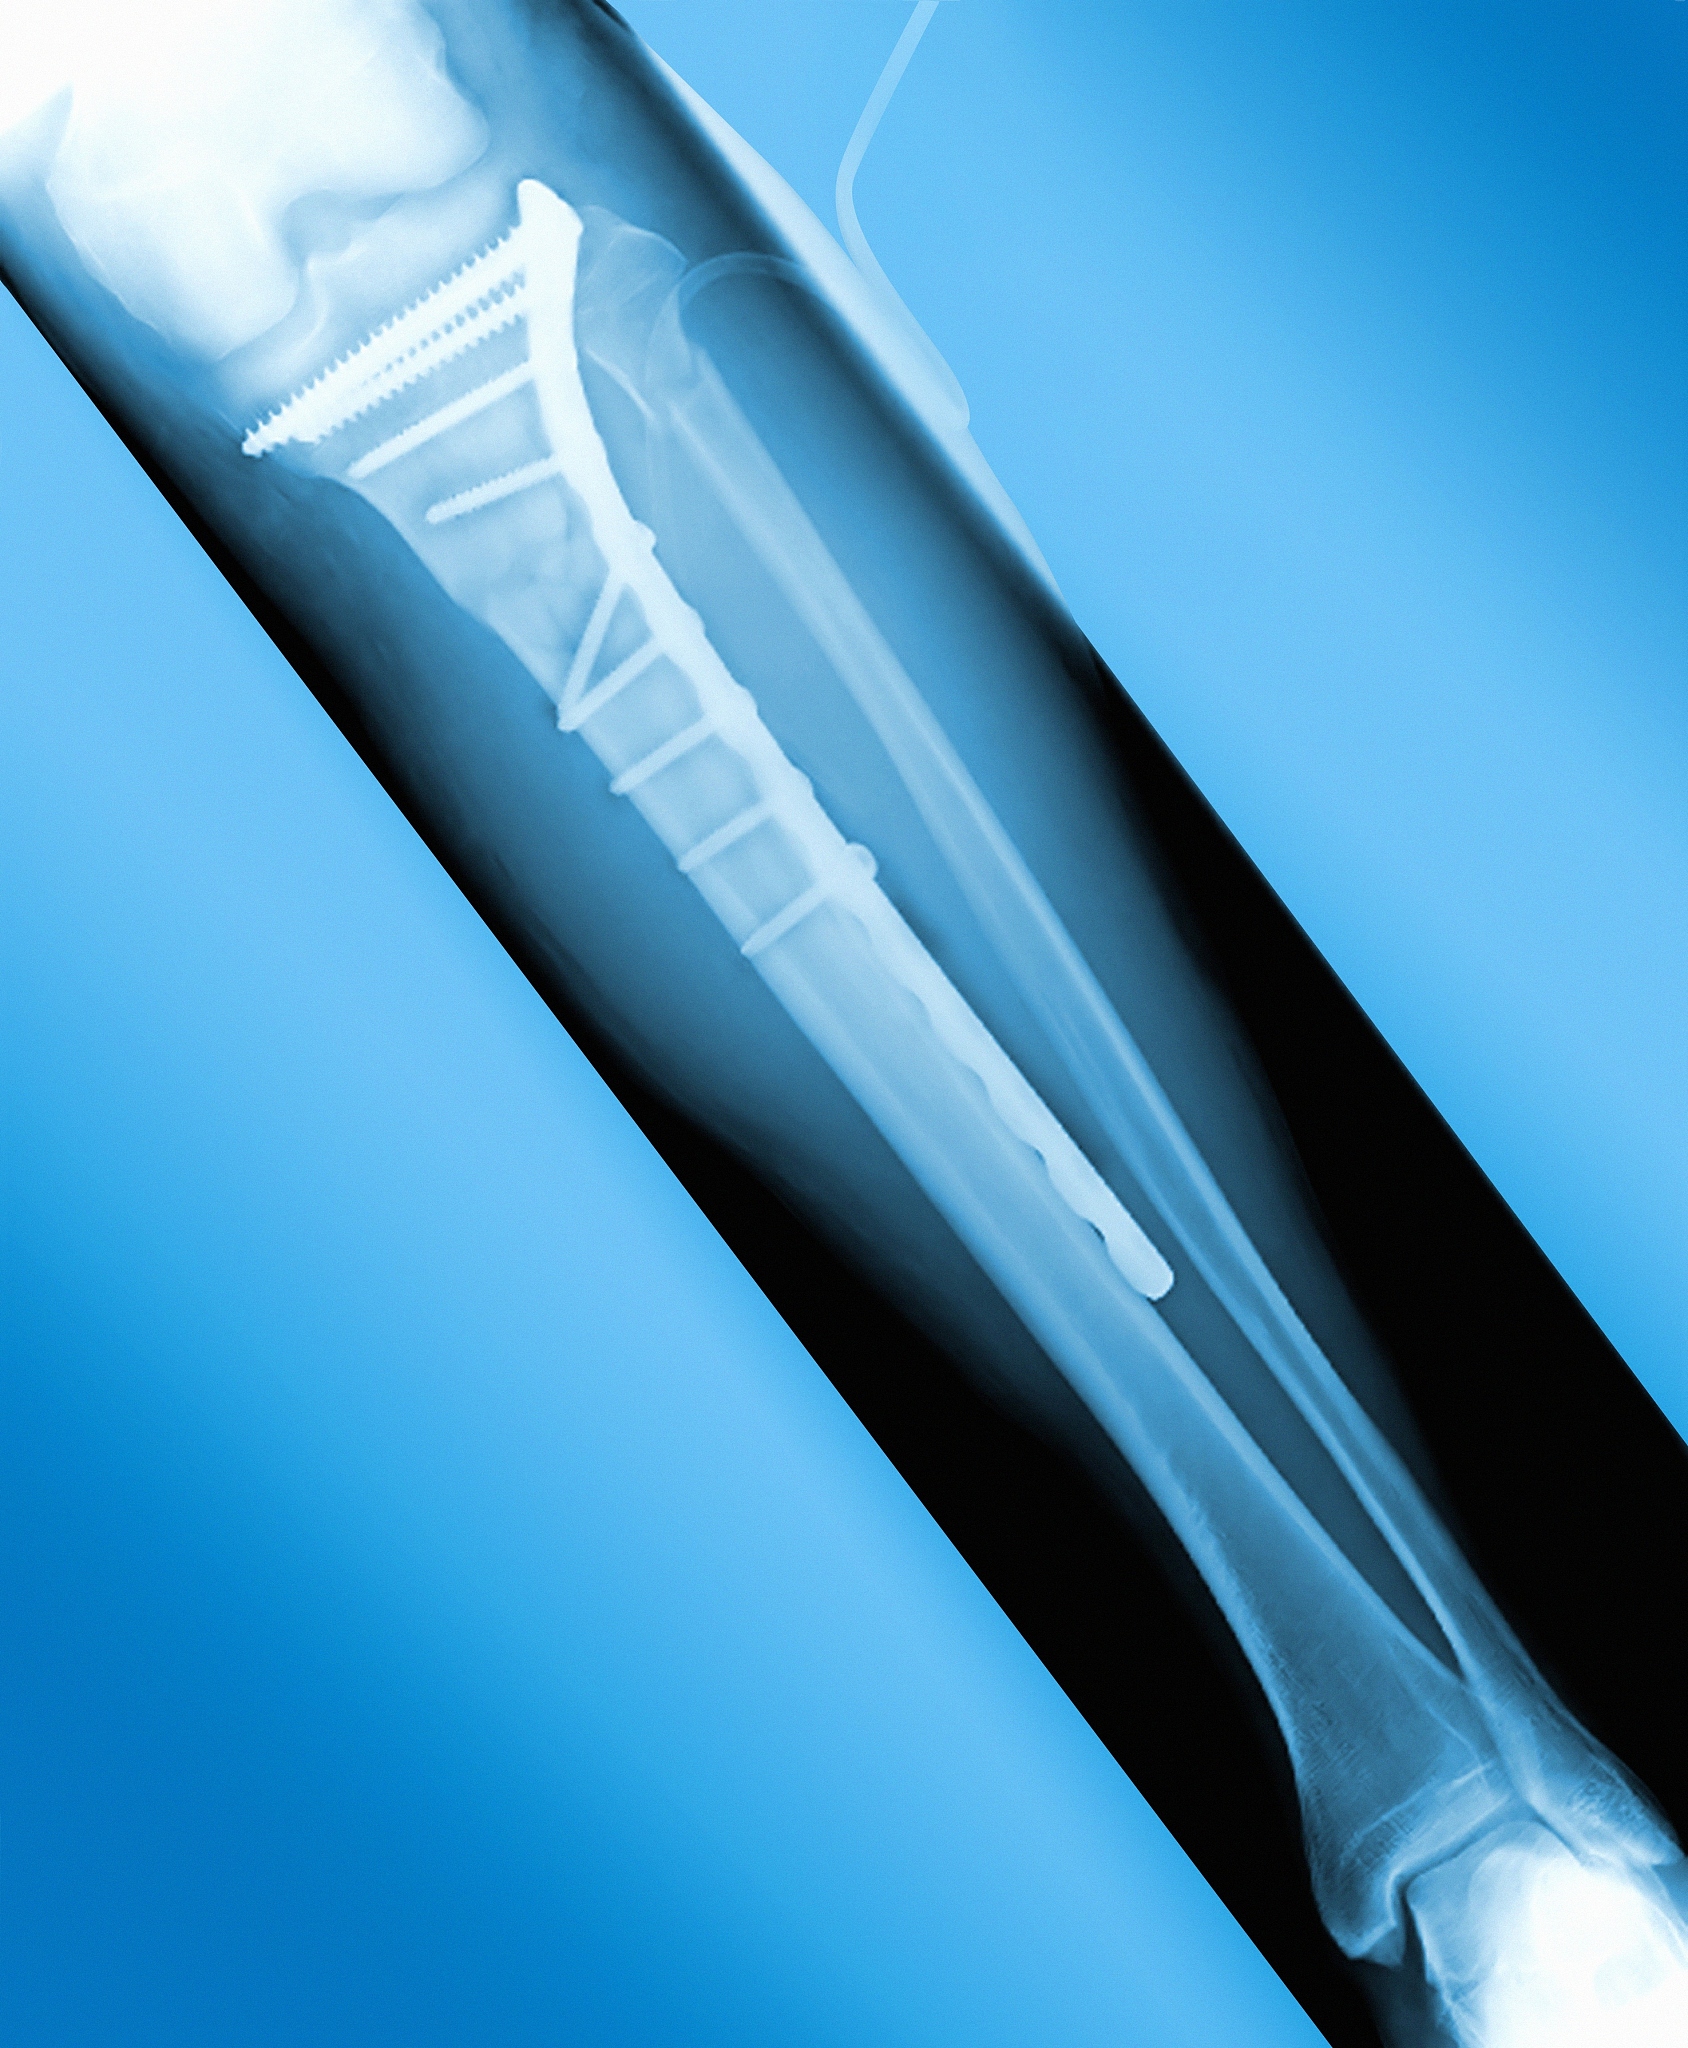

股骨近端防旋髓内钉内固定治疗高龄患者髋部骨折的优势包括:

1. 保留了患者的骨骼完整性:通过内固定手术,股骨近端防旋髓内钉可以将骨折部位重新定位并固定,保留了患者的骨骼完整性,有利于骨折的愈合。

2. 手术创伤小:相比传统的开放手术,股骨近端防旋髓内钉手术创伤较小,只需要进行几个小切口,减少了手术对患者的创伤。

3. 术后恢复快:内固定手术后,患者可以早期进行康复训练,恢复关节功能,减少了术后的康复时间。

4. 减少了感染和并发症的风险:内固定手术创伤小,术后感染和其他并发症的风险相对较低。

5. 对高龄患者的心肺功能要求较低:相比开放手术,内固定手术对患者的心肺功能要求较低,适合高龄患者进行手术治疗。

需要注意的是,股骨近端防旋髓内钉内固定手术也存在一些风险和并发症,如感染、内固定松动或断裂等,术前应充分评估患者的适应症和手术风险。

股骨近端防旋髓内钉内固定治疗高龄髋部骨折优势